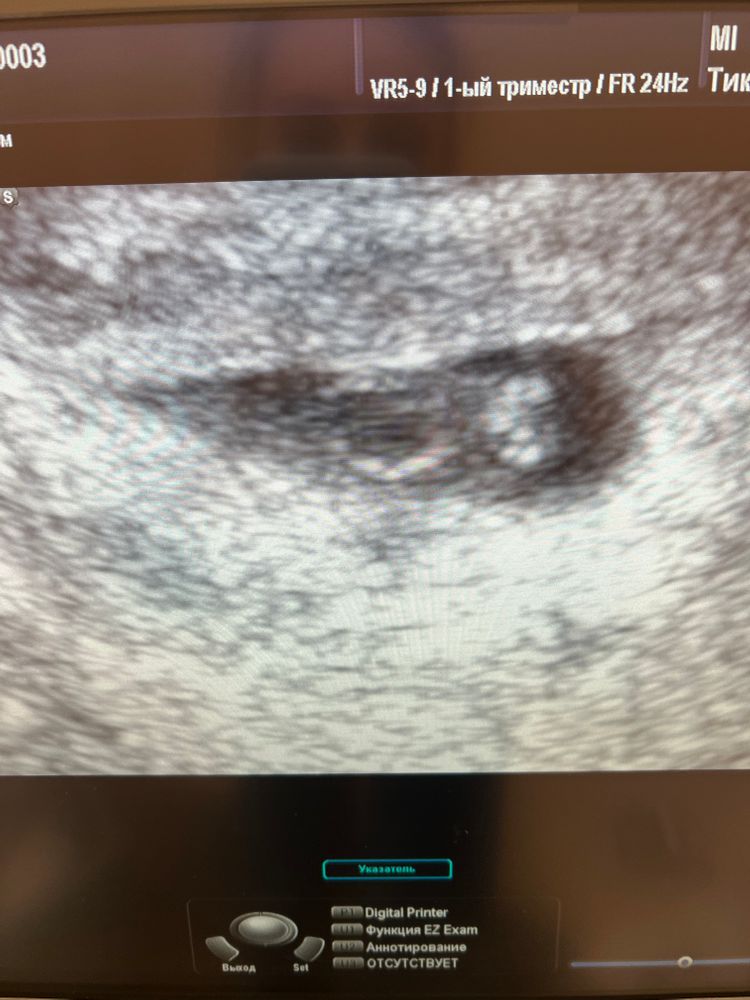

Второе узи😍

Annika, спасибо 🌸🌸 по М, 6н и 3д, по узи сказали 6н и 4д, в общем вровень)

УЗИ на 21 дпп после кровянистых выделений. Тянет матка после эро сна